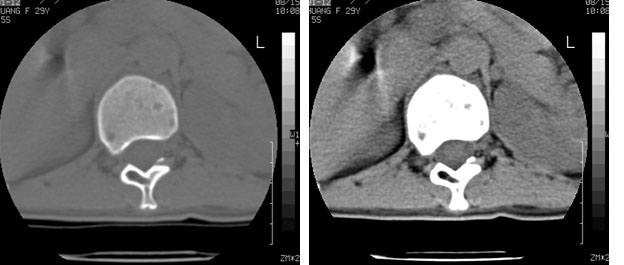

车祸致t12压缩性骨折,行ct扫描意外发现椎体多发肿瘤样病变,建议加拍骨盆平片,患者平常无症状。

考虑多发骨髓瘤可能性大。(骨松质内弥漫性分布,边缘清晰的溶骨性破坏,无硬化。睥脏增大,其内有多个圆形底密度影。淋巴瘤不除。

脾及椎体多发占位病变.

脾脏及椎体多发占位病变。首先考虑淋巴瘤,其次骨髓瘤。建议查本周氏蛋白

2/t12压缩性骨折。脾挫裂伤(建议继续扫描或b超检查)

椎体多发性溶骨性破坏,部分融合,椎旁无软组织肿块、椎间隙正常,t12 压缩,脾脏增大,其内示多发低密度影,首先考虑多发性骨髓瘤。病人较年轻,平素无异常,转移瘤可能性小。